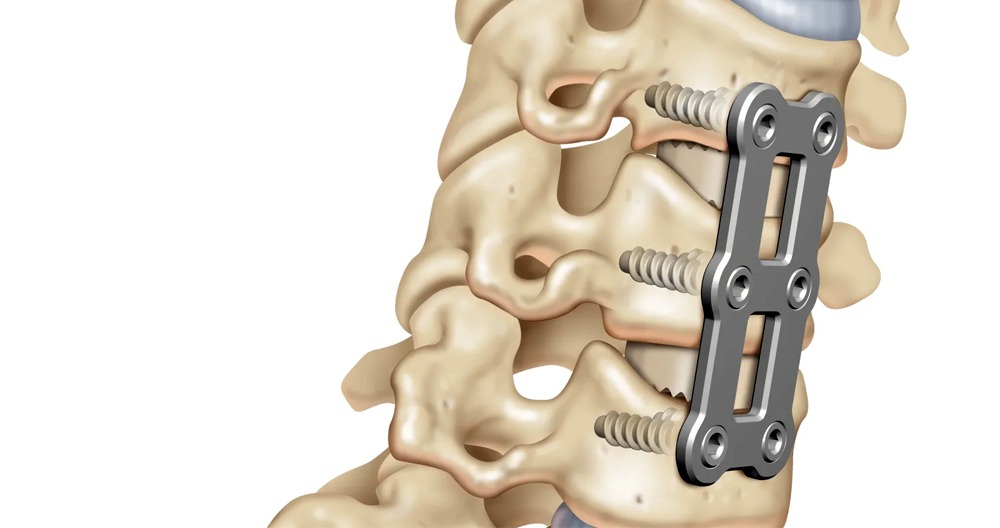

Spinal abnormalities usually involve the discs. These are soft, jellylike structures that act between the bones in your spinal column. They can become displaced or degenerate which can cause nerve compression or irritation. The foramen is the passageway through which the nerve exits the spinal cord, and can cause it to become compressed. Whatever the reason, these issues can easily be resolved by one of these three techniques:

Anterior Cervical Discectomy

An anterior cervical Discectomy is a procedure that treats disc problems such as herniation or degeneration. Your surgeon will access the spine through your anterior (or front) and remove the affected disc. Finally, a bone graft will be used to stabilize the region. She or he may also remove bone growths that press against your spinal nerve.